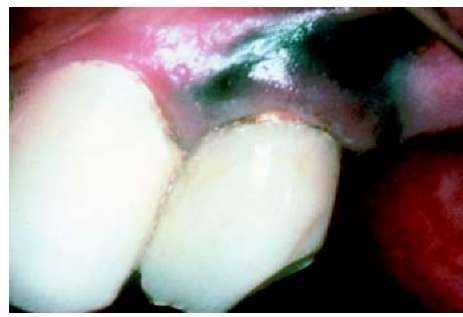

ДЕНТАЛЬНЫЕ СПЛАВЫ И ИХ УСТОЙЧИВОСТЬ ПРОТИВ КОРРОЗИИ На рисунке 9 отчетливо видна историческая работа этрусков, в которой посредством лигатур был зафиксирован естественный ряд зубов, а в качестве зубных протезов были использованы зубы животных. Интересным представляется тот факт, что структуры из драгоценных металлов, подвергавшиеся влиянию коррозии на протяжении 2 500 лет в недрах земли, выглядели как новые. Это еще раз доказывает, что золото и его сплавы являются идеальными материалами для изготовления зубных протезов. Следует избегать взаимного влияния между сплавами и тканями (рис.10), что может привести к патологическим явлениям. В этом случае именно продукты коррозии NiCrMo-сплава привели к данному заболеванию. После их удаления исчезли изменения на десне, и пациент перестал ощущать недомогание. Этот пример, как и многие другие, подчеркивает решающее значение выбора соответствующих материалов, влияющих на общее самочувствие пациента. Любой протез выполняет задачу не только исправления функционального дефекта, но он является интегральной составной частью организма и должен быть им принят. Существует целый ряд факторов, которые обязательно должен учитывать врач-стоматолог. Чтобы с самого начала исключить опасность негативных эффектов, производители дентальных сплавов обязаны строго контролировать при новых разработках коррозионное воздействие. Основой для этих тестов должно быть взаимовлияние между металлической коронкой и слюной, а также через цементный стык с жидкостью человеческого организма (рис. 11). В связи с тем, что химический состав натуральной слюны очень сложный и сильно отличается от пациента к пациенту, то очень важно для экспериментов в лаборатории (in vitro) использовать стандартный коррозионный раствор, идентичный естественной слюне (0,1 моляра молочной кислоты/раствор поваренной соли, pH = 2,3). На рисунке 12 показано проведение данного опыта. Отлитые образцы разной геометрической формы и по-разному обработанные помещались в раствор при температуре 37 °С. Через 7 дней данные образцы вынимали из жидкости и подвергали анализу различными методами (AAS, ICP) на определение возможного содержания ионов металлов. Потеря массы определялась в мг/см2. Несмотря на то, что потеря массы сплавов из драгоценных металлов в подобном опыте чрезвычайно мала, различие между типами сплавов удалось, тем не менее, установить. На рисунке 13 продемонстрировано такое сравнение между сплавами с высоким содержанием золота (Herador H), с редуцированным содержанием золота (Heraloy G) и сплавами с содержанием палладия (Albabond U). Анализировалось наличие отдельных компонентов сплавов. Четко прослеживается, что освобождение ионов металлов в сплавах с высоким содержанием золота (голубой цвет) экстремально незначительно, а вследствие этого, не подвергается аналитическому учету. В сплавах с редуцированным содержанием драгоценных металлов (красный цвет) заметно содержание ионов палладия, индия, галлия. Самые высокие показатели при освобождении ионов палладия, меди, индия и галлия наблюдаются у сплавов с содержанием палладия (зеленый цвет). |

Этот эффект со сплавами, содержащими драгоценные металлы и медь, можно использовать в рамках профилактики вторичного кариеса. На рисунке 20 показано освобождение ионов меди во влажный стык цемента. Внедрившиеся в него бактерии обезвреживаются ионами меди и в меньшей степени освободившимися из цинкофосфатного цемента ионами цинка. УДАЛЕНИЕ ОКСИДОВ ПО КРАЮ КОРОНКИ ПУТЕМ ПРОТРАВЛИВАНИЯ Как было сказано выше, следует избегать местного обогащения ионами металла в переходной складке полости рта, так как в противном случае высокие концентрации ионов металлов токсично влияют на соседние ткани. Эта проблема особенно быстро возникает, если край коронки из сплава, облицованного прежде керамикой, не освободился полностью от остатков оксидов, легко растворяемых в слюне (рис. 21). Оксиды растворяются находящейся в переходной складке слюне, которая часто имеет очень низкий показатель pH. Геометрические соотношения в переходной складке ограничивают обмен между слюной в ней и полостью рта. Это приводит к тому, что концентрация ионов металлов в переходной складке может быть очень высокой, ионы вступают в контакт с десной и как следствие - воспаление и изменение расцветки (потемнение) (рис. 22, 10). Эти негативные явления можно избежать, если при керамическом обжиге после завершения всех работ (после полировки) удалить неизбежно возникающие оксиды в процессе 10-минутного протравливания. Этот процесс при участии сульфокислоты должен длиться не более 15 минут, иначе может быть нанесен ущерб созданному сцеплению металла с керамикой. Описанные патологические изменения при применении сплавов с высоким содержанием золота на практике встречаются редко. В связи с этим встает вопрос о влиянии различных типов сплавов. Чтобы суметь основательно ответить на него, сплавы подвергали термической обработке аналогично обжигу керамики. Результатом явилось большое различие в соотношении окисления керамических сплавов с высоким содержанием золота и сплавов на базе палладия. На рисунке 23 (вверху) виден разрез оксидированного керамического сплава с высоким содержани-